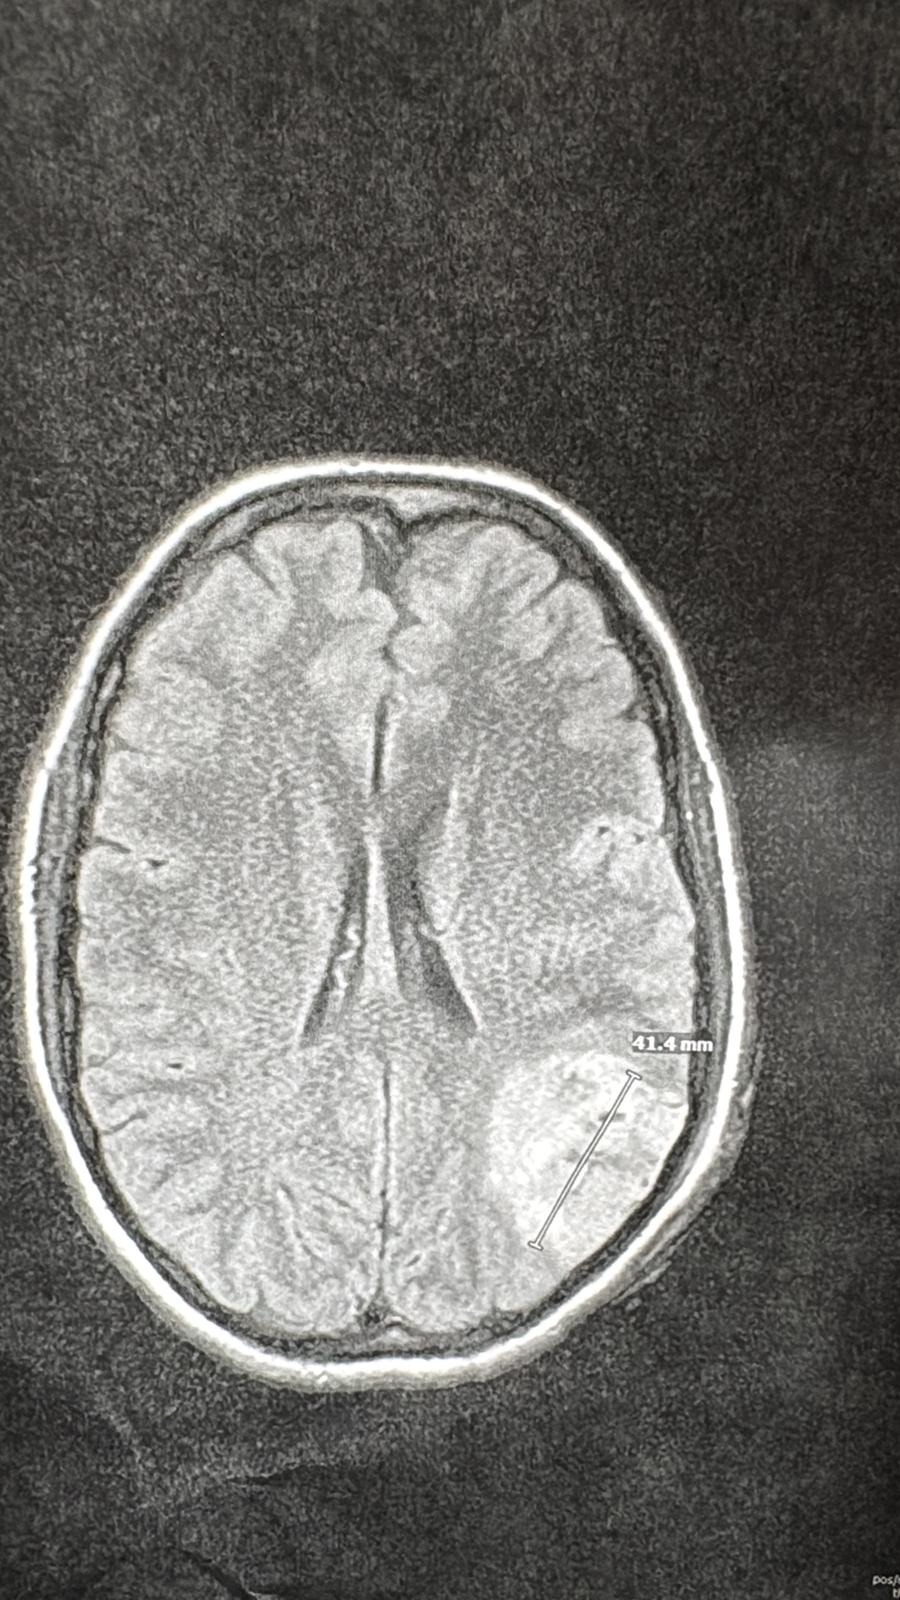

Less than two months after welcoming their beautiful baby girl, Ahava (Havie), Jo suffered a sudden and terrifying seizure. She lost consciousness and was rushed to the hospital, where an MRI revealed she had a brain tumor.

In the days that followed, Jo had multiple debilitating seizures and had to be intubated. On May 26, she underwent brain surgery. Doctors were able to remove part of the tumor, but because of its location, not all of it could be taken out.

Pathology confirmed the tumor is an Oligodendroglioma, a rare form of brain cancer. While it does carry some positive and encouraging genetic markers, such as 1p/19q codeletion and IDH1 mutation, described by her doctors "as good signs." Jo is now facing a lifetime of managing this disease.

The next MRI, scheduled for late August, will help determine if the tumor is growing. Regardless, Jo will need chemo, radiation, or a targeted treatment using HDAC inhibitors. It’s a long road ahead, physically, emotionally, and financially.